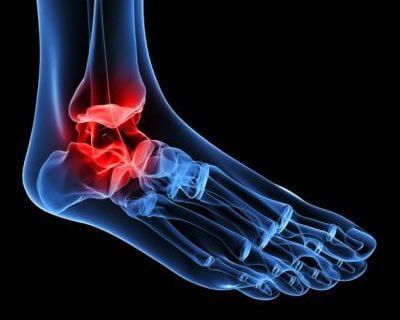

Hvordan artrose i anklene oppstår

Denne typen artrose er forårsaket av progressiv slitasje på brusken i ankelleddet. Det er vanlig at våre ankler blir stive og utvikler deformiteter etterhvert som vi blir eldre.

Klassiske leddhevelser kan også vises, noe som gjør det til en svært smertefull, samt begrenset, tilstand.

Hva er symptomene på artrose i ankelen?

Den første advarselen på slitasje på brusken i dette leddet er smerte når vi går. I begynnelsen legger vi merke til det etter en lang tur.

- Trykk eller mer spesifikk skarp smerte i ankelområdet kjennes når du går, noe som tvinger oss til å hvile anklene i noen minutter for å lindre smerten.

- Senere kan anklene bli hovne, og det kan også være vanskelig å bruke en bestemt type fottøy.